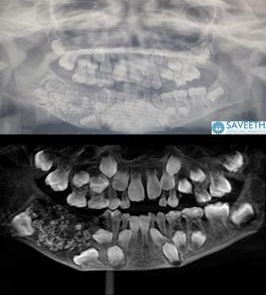

Quando tutto è finito, i genitori devono aver tirato un sospiro di sollievo. È indiano l’intervento record, durato cinque ore, su un bambino di sette anni a cui sono stati rimossi 526 denti. L’operazione, effettuata a Chennai (India), è stata eseguita dopo che il piccolo era stato portato al “Saveetha Dental College” con una mascella molto gonfia. «Questo è il primo caso in assoluto documentato in tutto il mondo in cui sono stati trovati così tanti piccoli denti in un singolo individuo», hanno commentato i medici.

Si tratta dell’odontoma composto, una condizione che porta a un sovranumero di germi dentari. Nel bambino, i denti, ognuno di dimensioni da 0,1 a 15 millimetri, si trovavano in una sacca della mascella inferiore. I chirurghi hanno detto che anche il pezzo più piccolo aveva una corona, una radice e lo smalto. «I genitori del bambino hanno fatto visitare il figlio per la prima volta in ospedale quando aveva tre anni, dopo aver notato il gonfiore nella mascella inferiore destra, ma il bimbo non aveva collaborato con i medici, e la sua condizione all’epoca non era stata diagnosticata. Così la massa è aumentata, arrivando ad assumere i contorni di una sacca e a pesare circa duecento grammi».